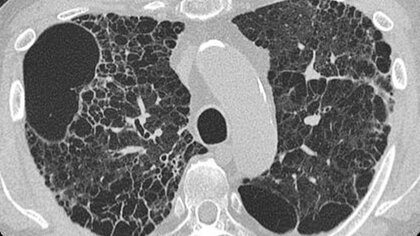

ただの肺炎のはずが…難病と診断され余命宣告 移植手術で回復も専門医「せき、息切れが増えたら受診を」【福島発】